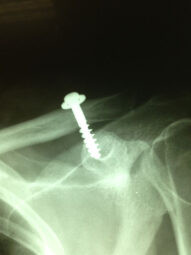

Fractura de Tibia Distal